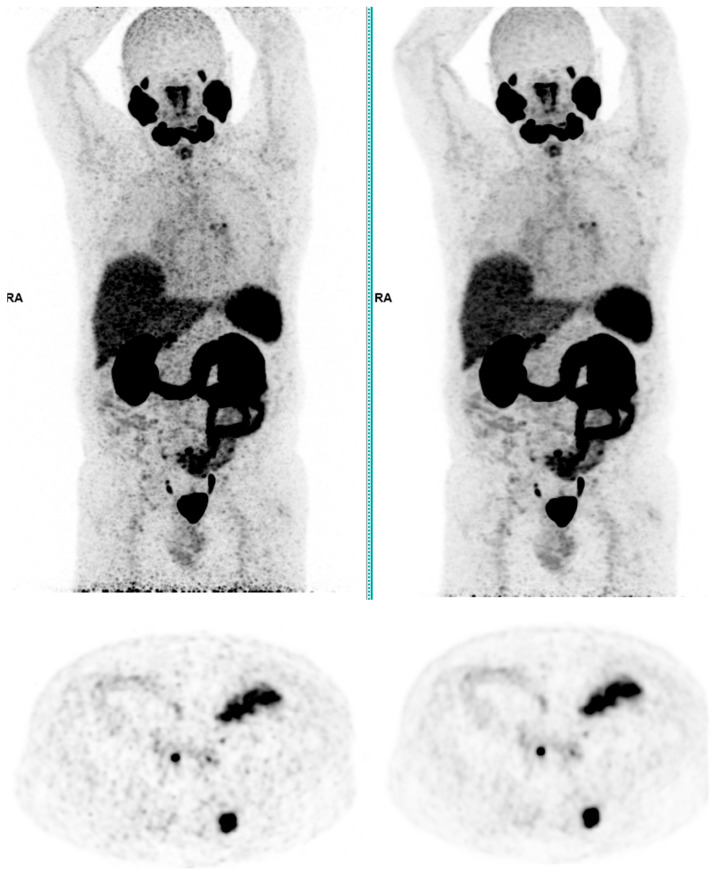

This study assesses the clinical deployment of SubtlePET™, a commercial AI-based denoising algorithm, across three radiotracers-18F-FDG, 68Ga-PSMA-11, and 18F-FDOPA-with the goal of improving image quality while reducing injected activity, technologist radiation exposure, and scan time. A retrospective analysis on a digital PET/CT system showed that SubtlePET™ enabled dose reductions exceeding 33% and time savings of over 25%. AI-enhanced images were rated interpretable in 100% of cases versus 65% for standard low-dose reconstructions. Notably, 85% of AI-enhanced scans received the maximum Likert quality score (5/5), indicating excellent diagnostic confidence and noise suppression, compared to only 50% with conventional reconstruction. The quantitative image quality improved significantly across all tracers, with SNR and CNR gains of 50-70%. Radiotracer dose reductions were particularly substantial in low-BMI patients (up to 41% for FDG), and the technologist exposure decreased for high-exposure roles. The daily patient throughput increased by an average of 4.84 cases. These findings support the robust integration of SubtlePET™ into routine clinical PET practice, offering improved efficiency, safety, and image quality without compromising lesion detectability.